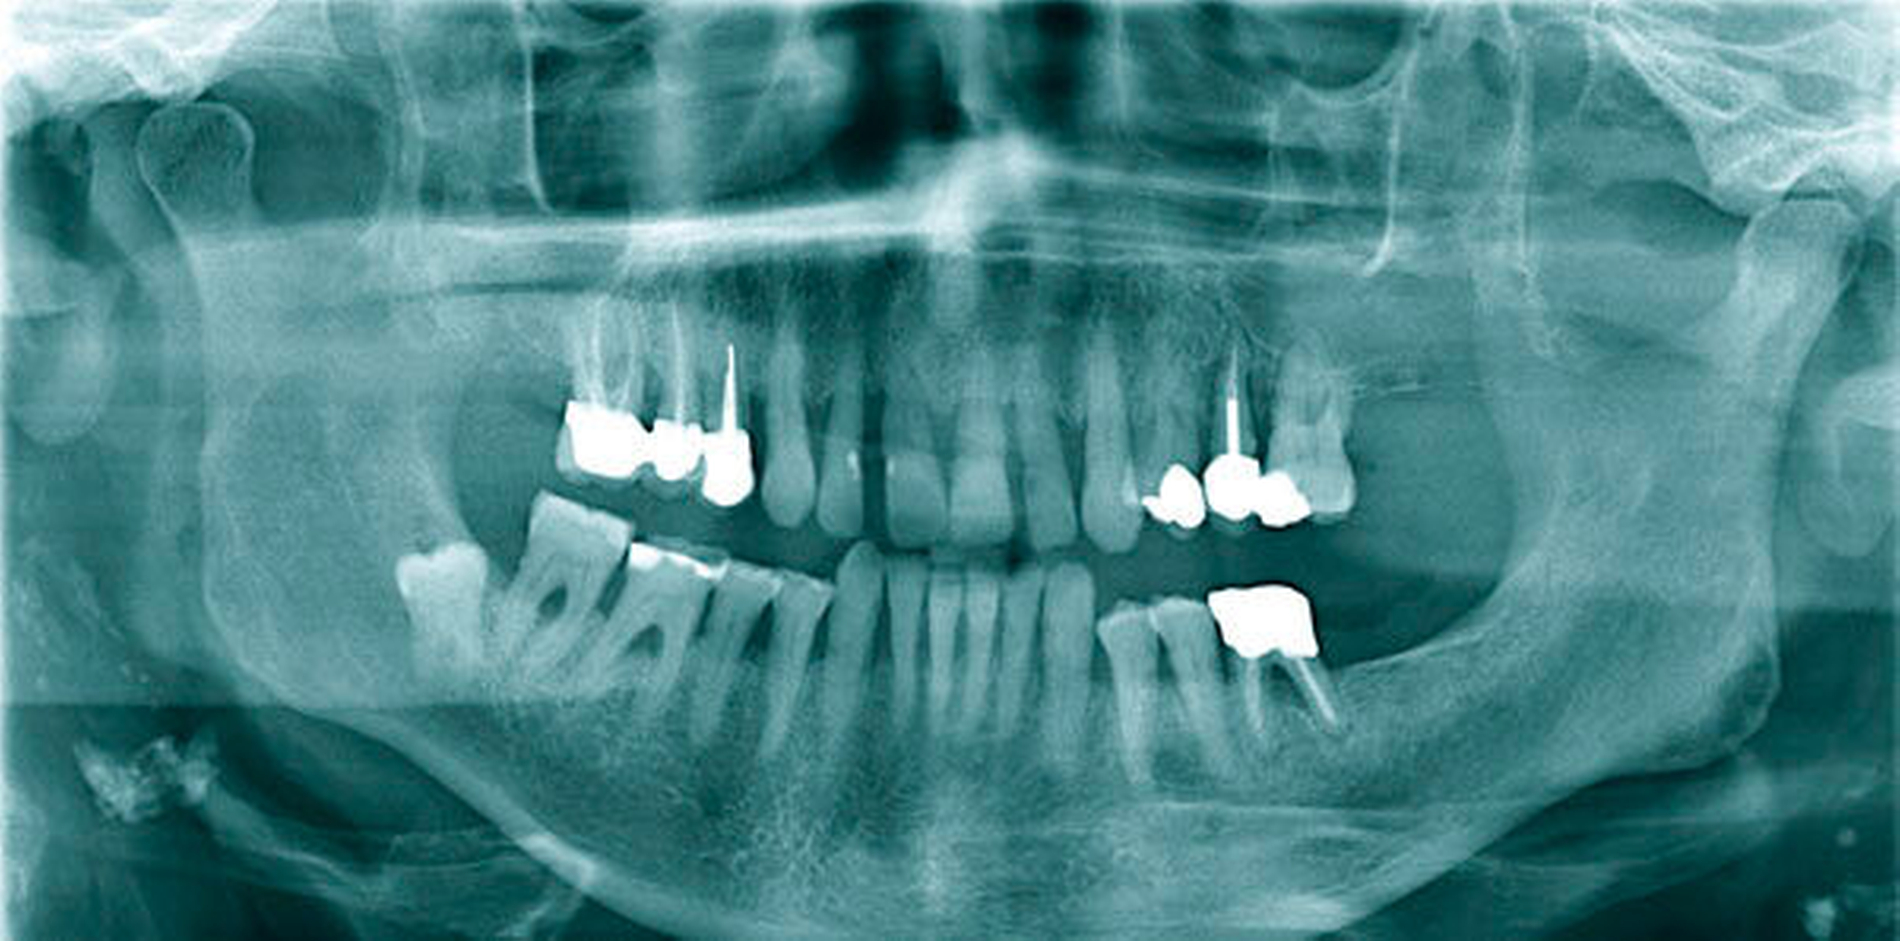

Zum Zeitpunkt der Untersuchung zeigte sich im linken Oberkiefer palatinal regio 26/27 ein livider braun-rötlicher Tumor von etwa zwei Zentimeter Größe mit Verdrängung der fixierten Gingiva nach krestal. Nach palatinal-medial war das Bindegewebe unter reizloser Schleimhaut aufgetrieben (Abbildung 1). In der Bildgebung mittels Panoramaschichtaufnahme zeigte sich in der interessierenden Region eine Verschattung der linken basalen Kieferhöhle mit Auflösung des krestalen Knochens im Molarenbereich. Des Weiteren war ein retinierter Zahn 48 und ein horizontal-vertikaler Knochenabbau bei bekannter Parodontitis zu erkennen (Abbildung 2). Zur weiteren Diagnostik wurde eine Computertomografie des Kopfes und bei Verdacht auf mögliche Metastasierung der vorbekannten Malignome eine Computertomografie des Thorax und Abdomens durchgeführt. Hierbei zeigte sich die bereits diagnostizierte Raumforderung im Bereich der linken basalen Kieferhöhle mit partieller Auflösung des molarennahen Knochens und einer weichteildichten Raumforderung im Bereich der basalen Kieferhöhle. Die kranialen Anteile der Kieferhöhle waren belüftet (Abbildung 3). Ein Anhalt für eine Metastasierung oder ein Rezidiv des Urothel- bzw. Prostatakarzinoms bestand nicht. In dem durch eine Inzisionsbiopsie in Lokalanästhesie entnommenem Gewebe zeigte sich histologisch eine teils glandulär, teils kribriform konfigurierte epitheliale Proliferation mit teils basophilem Stroma. Es lag eine deutliche Positivität für CK7 und S100 ohne Färbereaktion für CK5/6 vor. Somit entsprach der Befund dem eines kanalikulären Adenoms. Der Tumor wurde in Intubationsnarkose entfernt. Zur Kieferhöhle bestand eine dünne knöcherne Abgrenzung, die belassen wurde. Eine endoskopische Untersuchung über den mittleren Nasengang zeigte bis auf zwei kleinen Schleimretentionszysten oberhalb der Läsion – die jeweils entfernt wurden – keine weiteren Auffälligkeiten. Der Defekt wurde durch eine Einlagerung des Bichat’schen Fettkörpers und eines Mukoperiost-Lappens von vestibulär gedeckt. Die finale histologische Beurteilung bestätigte die Diagnose und eine vollständige Entfernung. Nach einem unkomplizierten postoperativen Heilungsverlauf zeigte der Patient in der klinischen Nachsorge nunmehr sechs Monate nach Operation keinen Anhalt für ein Rezidiv.

Zur Diagnostik kann entweder eine Magnetresonanztomografie oder bei knöcherner Beteiligung eine Computertomografie durchgeführt werden. Bei reinen Weichgewebstumoren der Oberlippe oder Wange kann auch eine Sonografie ausreichend sein. Das radiologische Bild entspricht einer gut abgrenzbaren Weichteilmasse mit mitunter lokal aggressivem Wachstum und knöcherner Destruktion [Smullin et al., 2004].